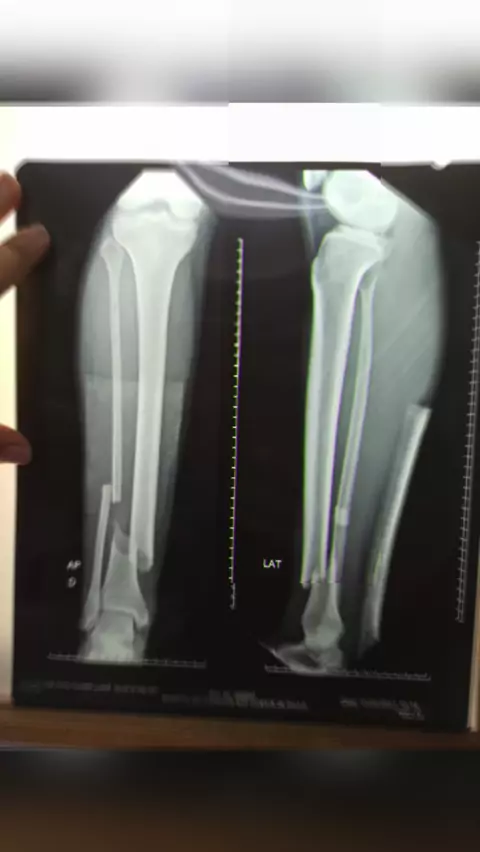

Reabilitação de fratura completa de Tíbia e Fíbula... 20 dias pós cirúrgico !